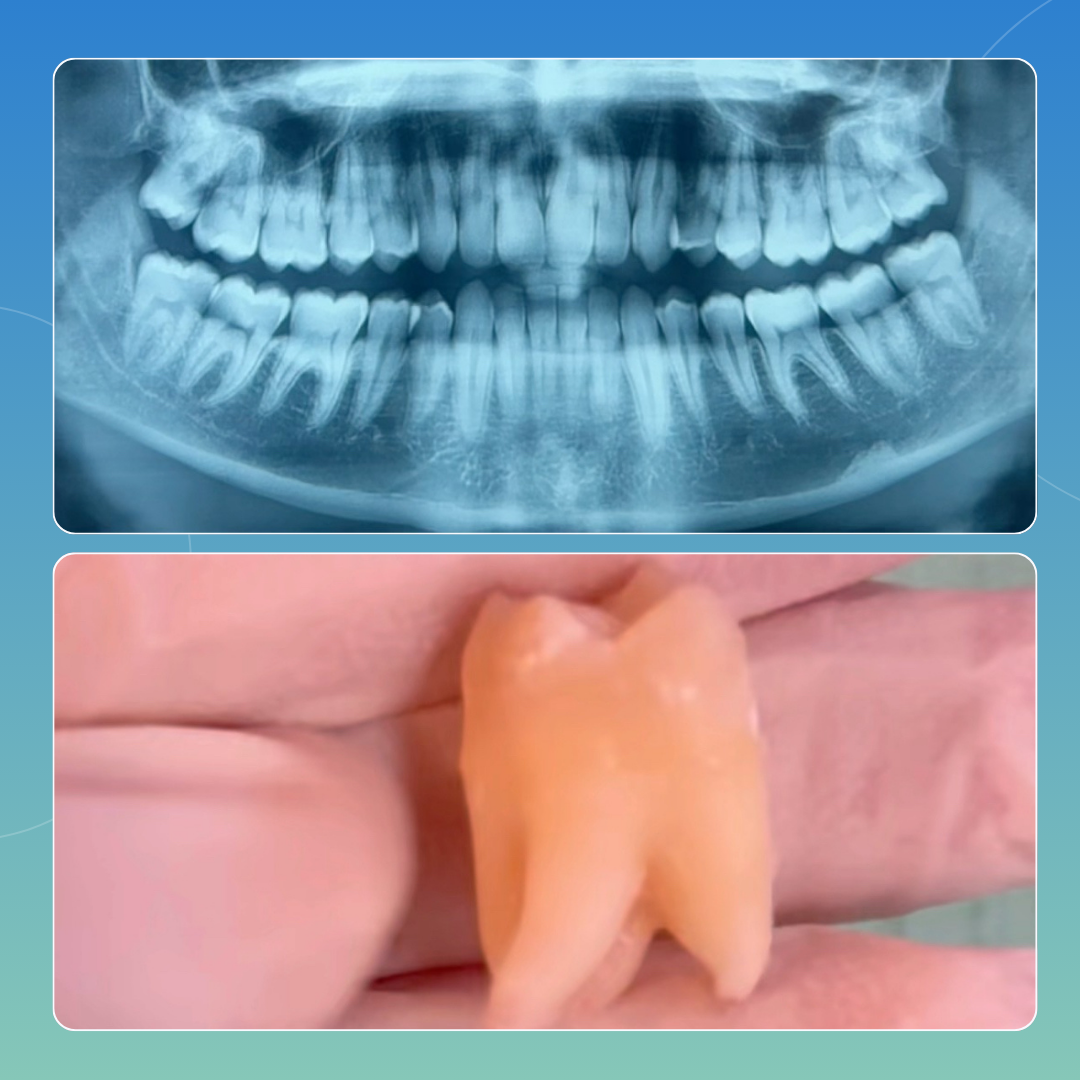

CASI CLINICI

Approccio personalizzato, esiti documentati

Di seguito riportiamo casi analizzati e svolti all’interno del nostro poliambulatorio che pensiamo possano rendere a pieno ciò che è per noi il nostro lavoro: passione e attenzione ai dettagli, volendo sempre il risultato migliore possibile che possa dar contentezza al paziente e a noi stessi